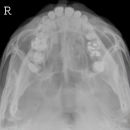

Nasennebenhöhlen (NNH)

Indikation

Lagerung

sitzend mit Gesicht zum Stativ

Hände festhaltend am Stativ

Rücken gerade

Mund weit geöffnet

Kinn liegt auf, Nase schwebt

Kopf anheben bis obere Zahnreihe und 1 QF über Ohr-Rand eine Linie bilden

Qualitätskriterien

Symmetrische Darstellung des Gesichtsschädels: seitengleiche Distanz zwischen lateralem Rand der Augenhöhle und äußerer Schädelkontur. Die Pyramidenoberkanten kommen unmittelbar unterhalb des Kieferhöhlenbodens zum Liegen, also in die obere Zahnreihe, sodass die Kieferhöhlen überlagerungsfrei zur Darstellung kommen.